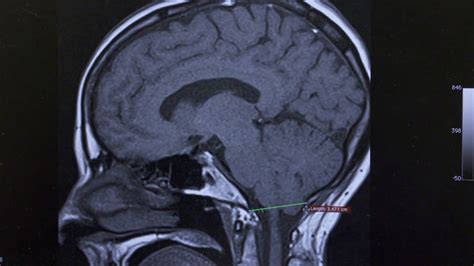

Receiving a diagnosis of Chiari malformation can be an overwhelming experience, often accompanied by a flurry of questions regarding long-term health and quality of life. This condition, which occurs when the lower part of the brain—the cerebellum—extends into the spinal canal, can cause a wide range of debilitating symptoms, including chronic headaches, neck pain, balance issues, and neurological deficits. Fortunately, medical advancements have paved the way for diverse Chiari malformation treatments that aim to relieve pressure on the brain and spinal cord, stop the progression of neurological damage, and improve overall patient function.

The severity of the condition often dictates the strategy. If left untreated, severe cases can lead to syringomyelia (the development of a fluid-filled cyst within the spinal cord), which significantly heightens the risk of permanent nerve damage. Therefore, timely diagnosis and professional evaluation are critical.

When conservative methods fail or when the anatomy presents a clear threat to neurological health, surgical intervention becomes the primary path. The most common and effective of the Chiari malformation treatments is a procedure known as posterior fossa decompression. The goal of this surgery is to create more space for the cerebellum and allow for the normal flow of cerebrospinal fluid (CSF).